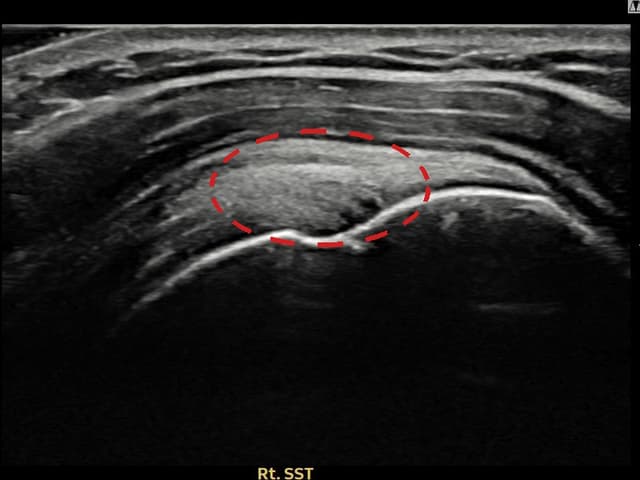

[経過期間: 22.08.10]

[石灰破砕吸引術] X線で右肩棘上筋腱内の石灰沈着(14mm × 10mm)を確認し、超音波ガイド下石灰破砕吸引術を施行しました。6本分の石灰を吸引し、術後4日後の追跡X線で石灰陰影の著明な減少を確認しました。